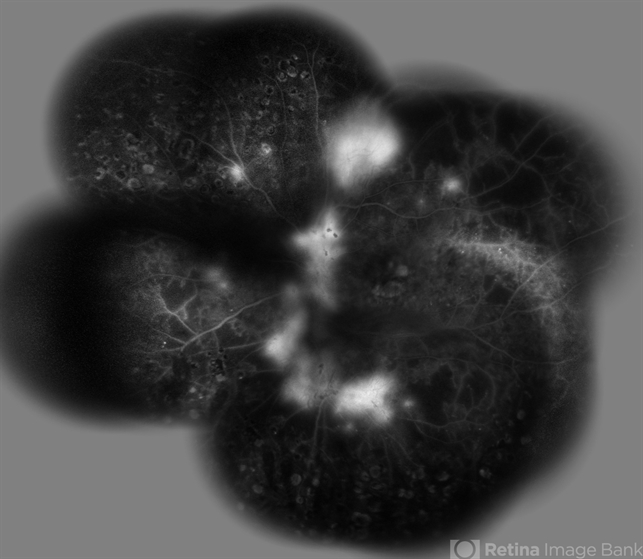

- proliferative diabetic retinopathy (PDR)

- Shabnam Pooreh, Negah Eye Center, Tehran, Iran

- Fundus camera

- Merged late phase FA image of the the right eye of a diabetic patient with PDR ; profound leakage from the NVD and NVE foci are present. Scars of previous scatter laser photocoagulation are visible.